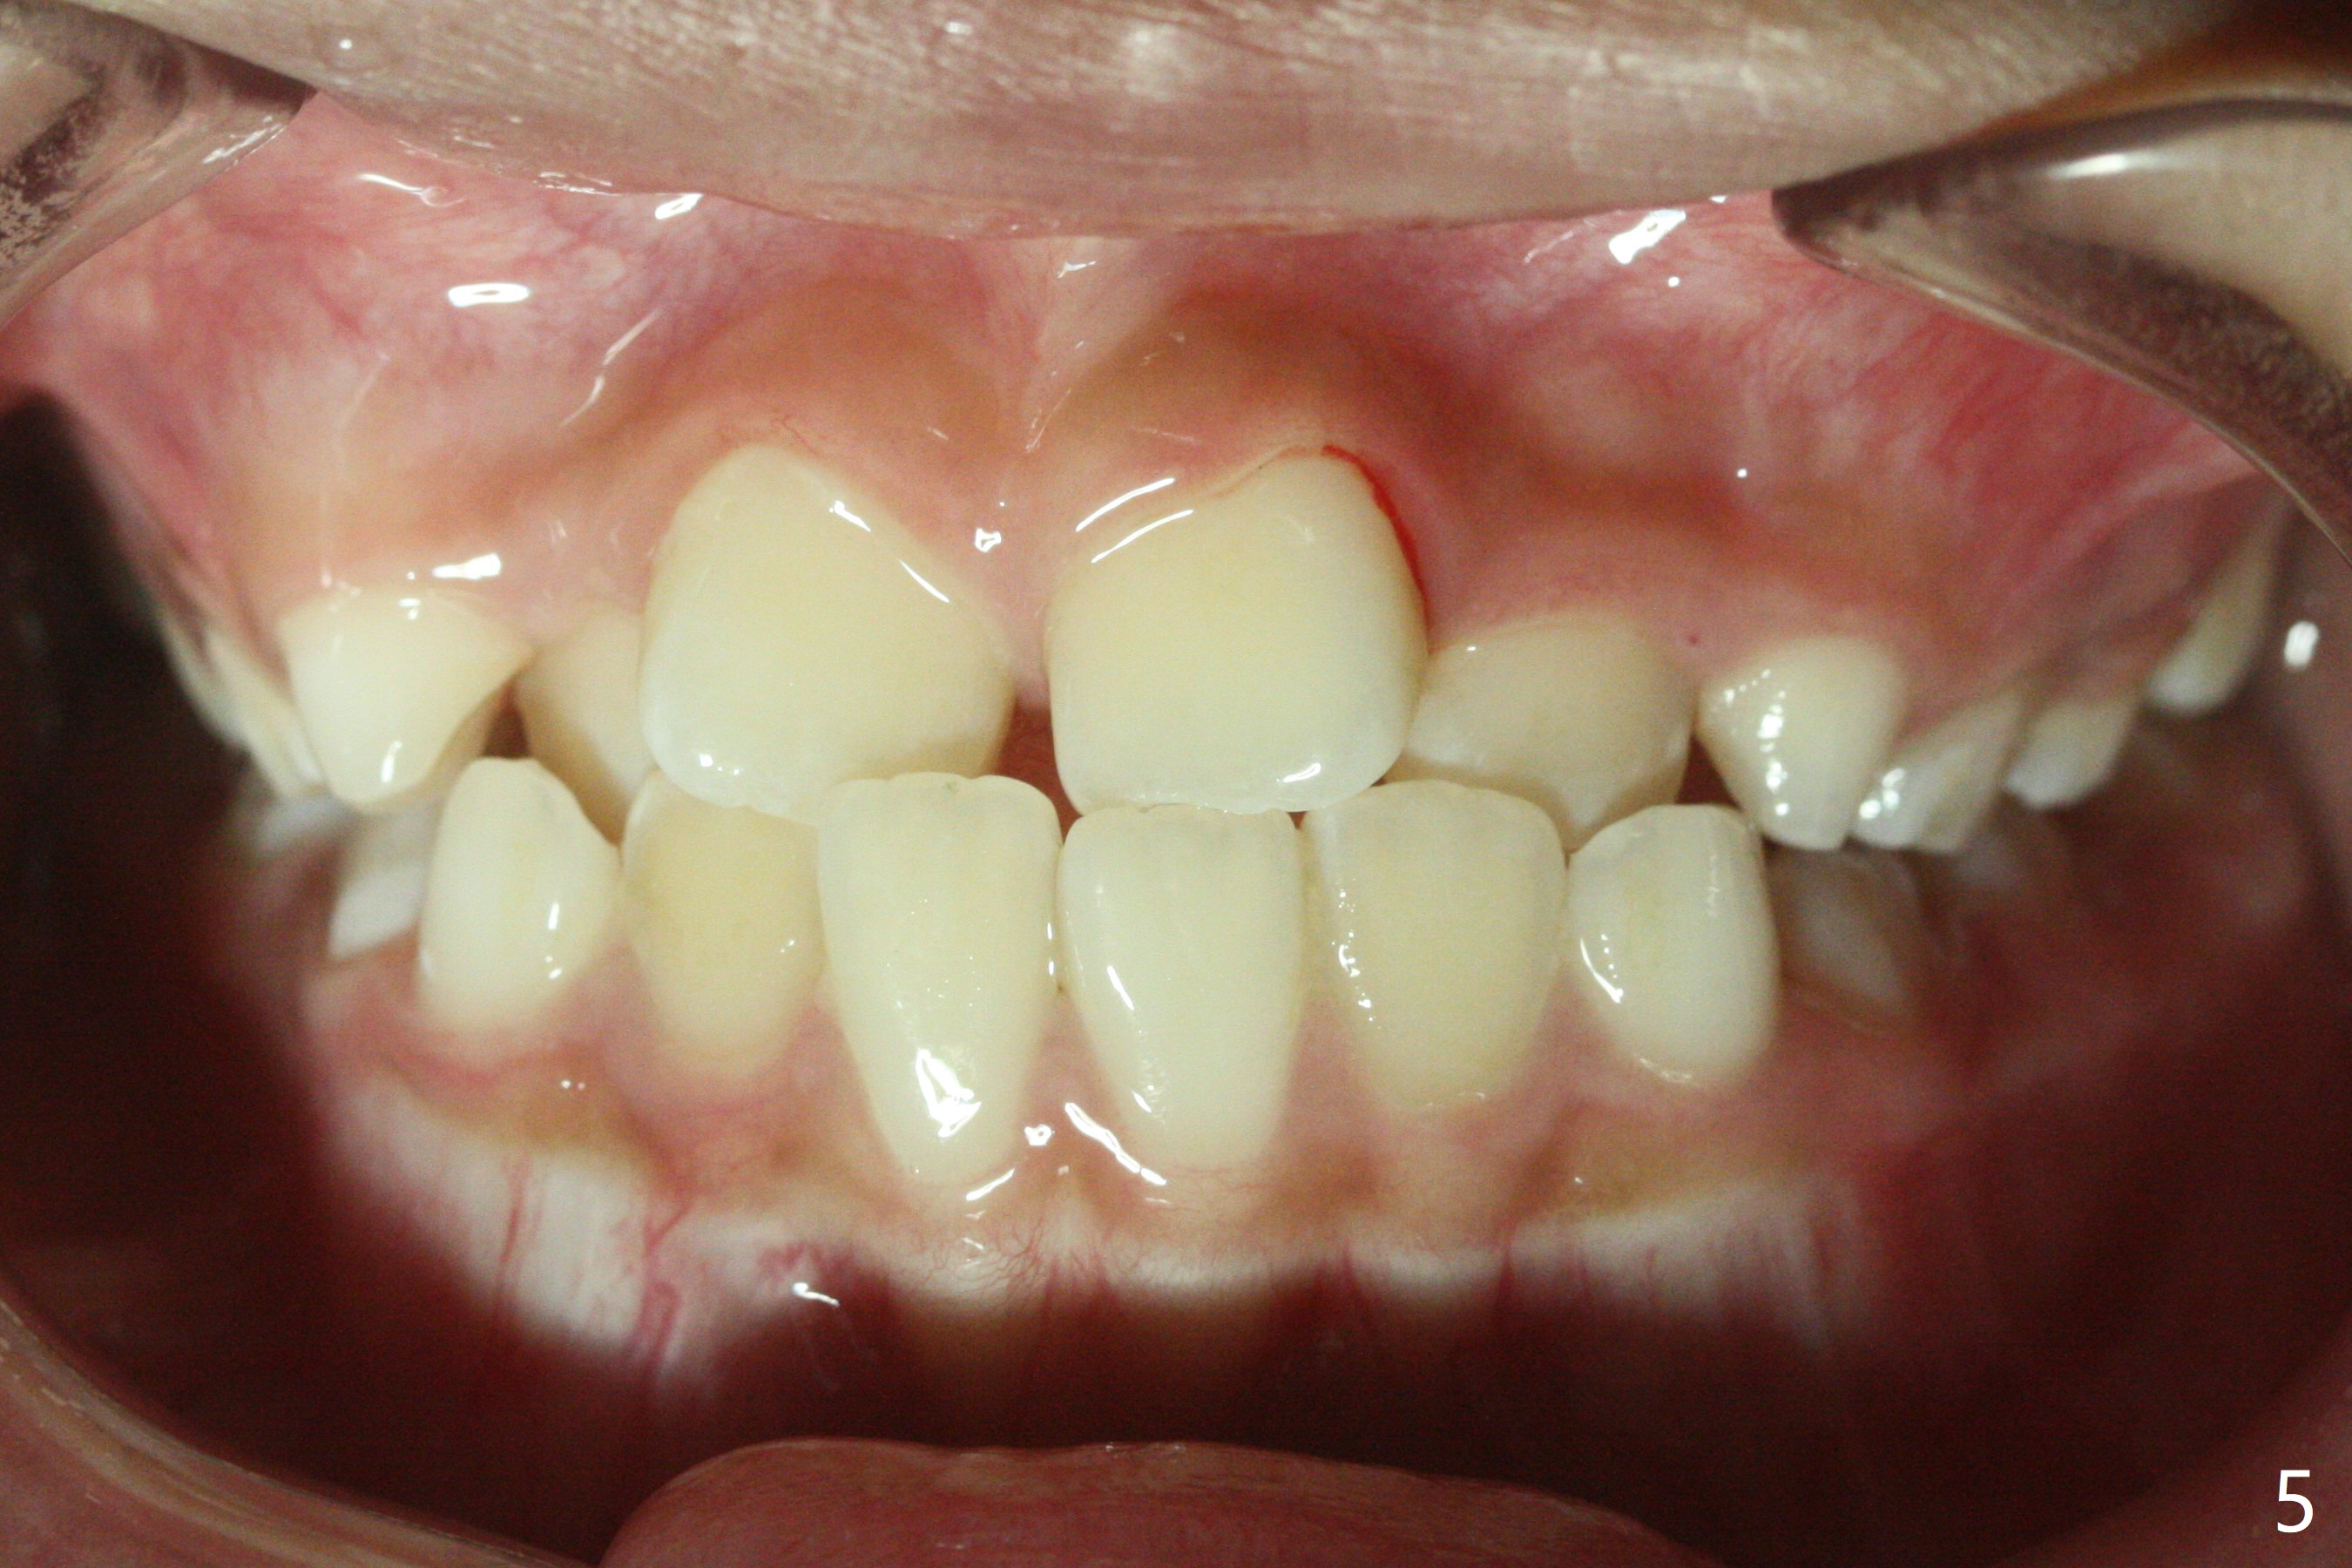

7岁女孩龋齿(图一)到八岁发展的严重(图二,三 (D))。为了有完整支抗,利用树脂(而不是不锈钢牙冠)保留左上第一乳磨牙(图六:D),以后可以安置矫正器。面部匀称(图七至十)。乳尖牙,第一恒磨牙:第一类咬合(图十一,十二)。左上前牙拥挤比右边轻,因为左上D龋齿破坏(图十三:D)。前牙扩弓时,右上D近中需要片切(^)。下颌拥挤轻(图十四),矫正器可以迟放置。